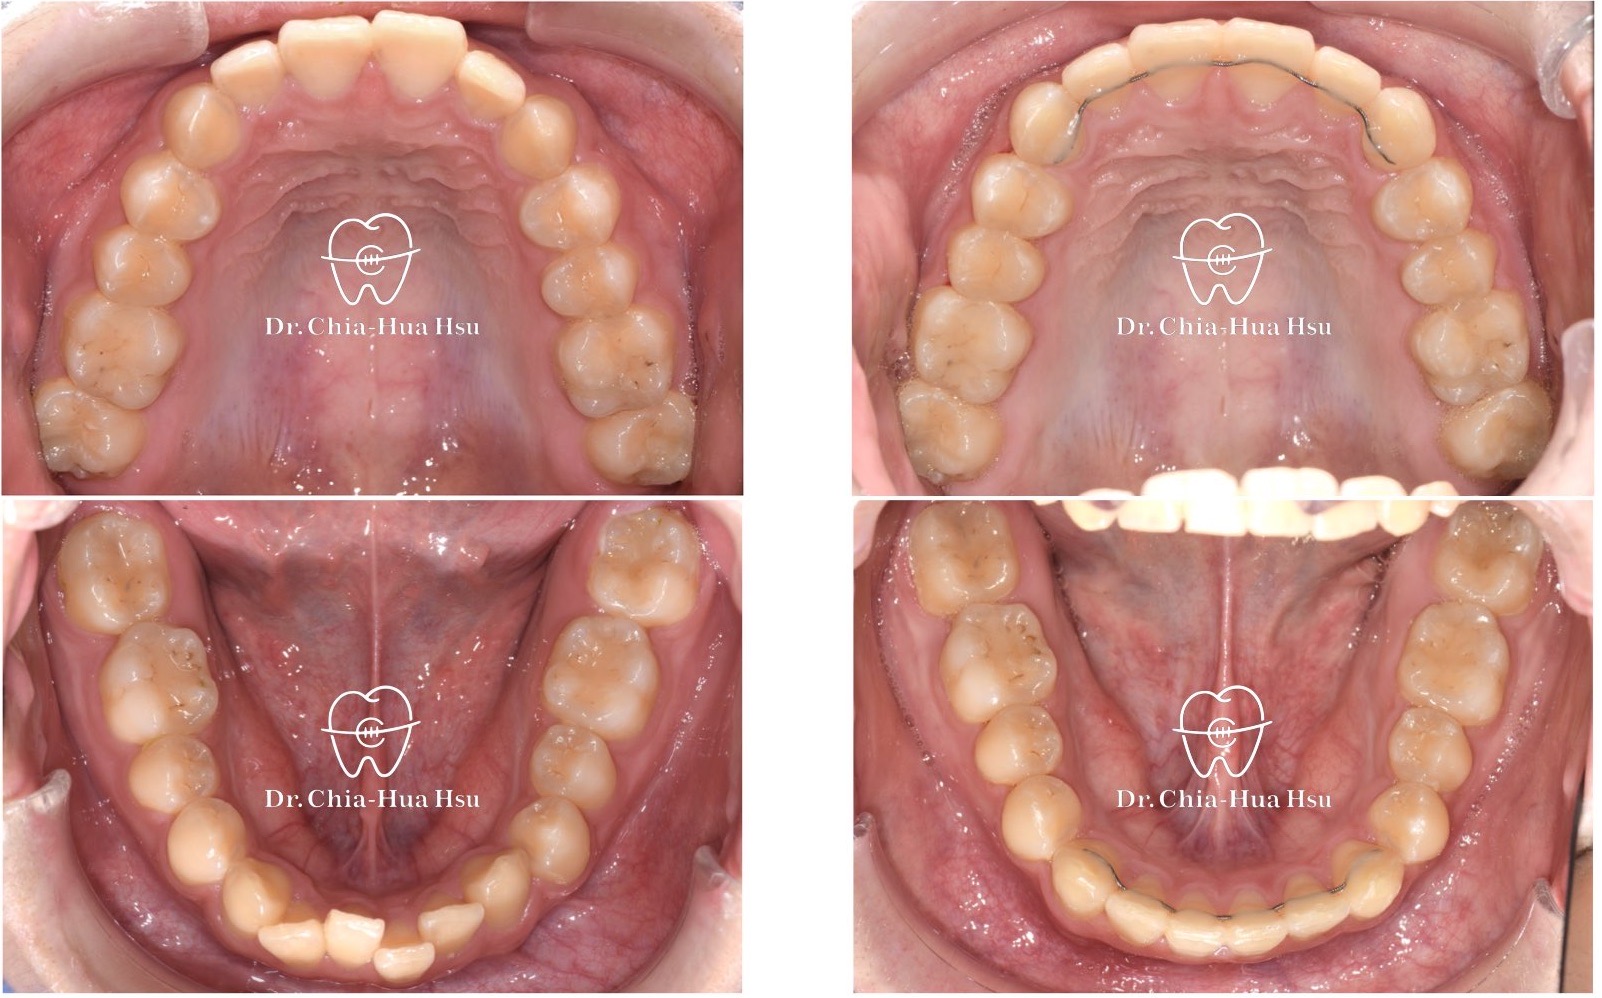

治療前

治療中

• 治療過程:治療過程使用『陰陽線』,來改善咬合平面歪斜的問題。

• 矯正小知識:『陰陽線』是利用特殊設計的 Beta-titanium arch wire (TMA) 線材(一條往上一條往下,像是太極的陰陽)來調整上顎咬合面的傾斜,改善患者的咬合面傾斜問題,並避免手術的痛苦。